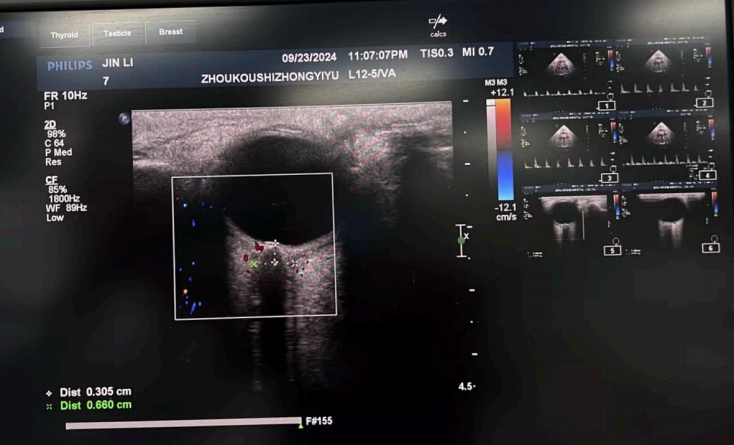

圖3:視神經(jīng)鞘直徑ONSD:評估顱腦?腫(操作者:吳威)